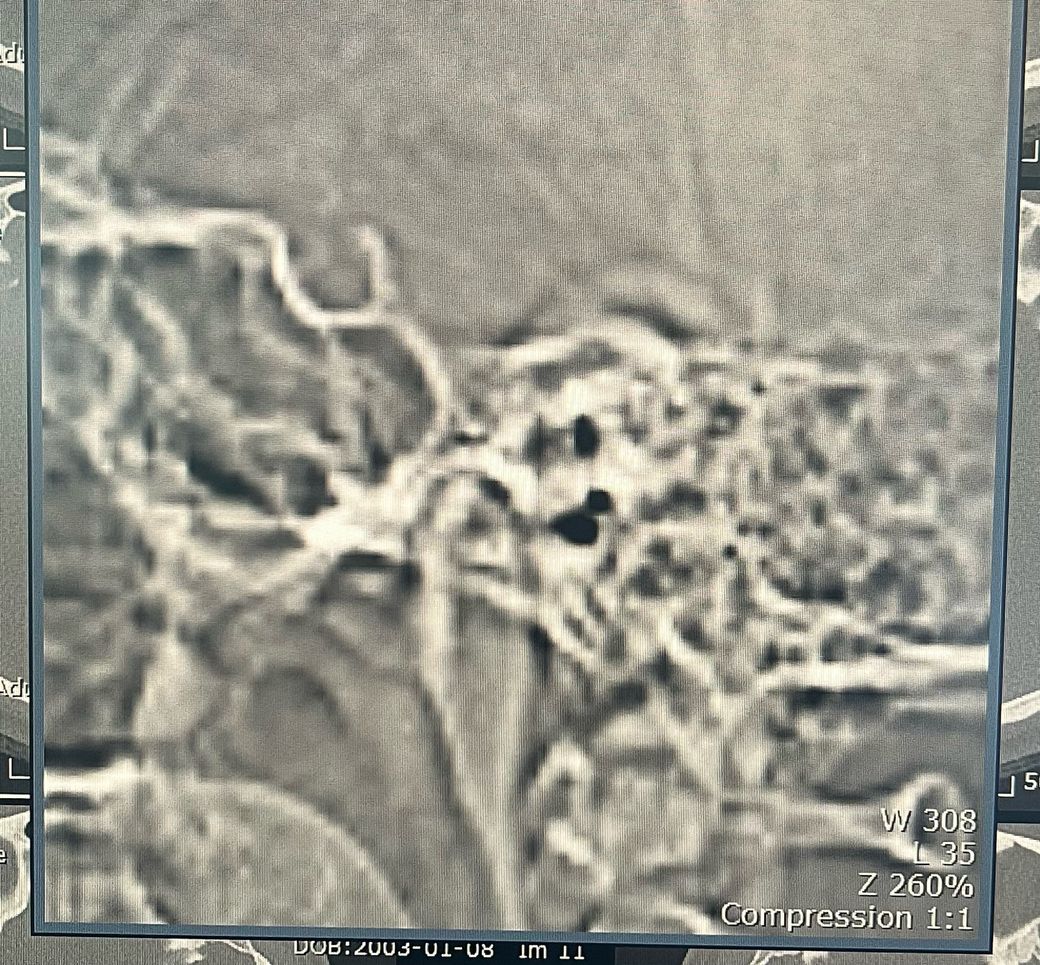

• 3번 째 사진

1. 턱디스크는 어떤 상태일까요 앞으로 빠져있나요?

2. 턱관절염 같은 턱관절 마모가 있나요

3. 턱에 염증이나 다른 이상이 있을까요

1. 엑스레이상 큰 문제는 발견되지 않습니다.

2. 단지 소리만 나는 것은 턱관절 질환으로 분류하지 않습니다. 소리가 나는 증상 외에 턱관절 통증, 입 안벌어짐 등의 증상이 동반된다면 구강내과 치과를 가보시기 바랍니다.

3. 모래 갈리는 소리가 난다면 턱관절염의 가능성이 있긴 합니다.